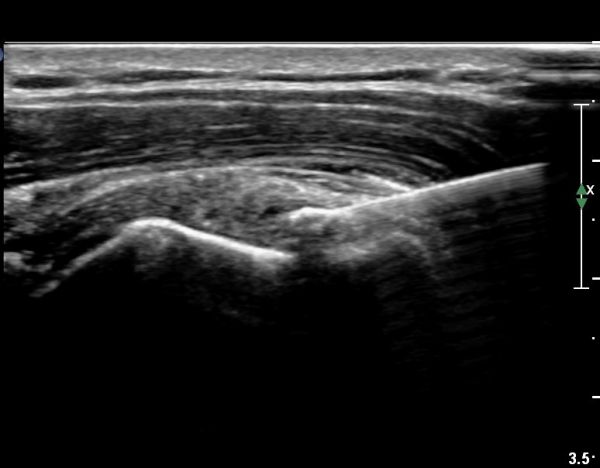

°ß°©ÇÏ±Ù°Ç ÁߺΠÁ¾´Ü¸é°Ë»ç¿¡¼­ ƯÀÌ ¼Ò°ßÀ» º¸ÀÌÁö ¾ÊÀ¸³ª(»çÁø 2) ŽÃËÀÚ¸¦ Á¶±Ý ÇϹæ(´Ù¸®ÂÊ)

À¸·Î À̵¿ÇÏ´Ï °ß°©Çϱٰdz»  ¼®È¸È­ µ¢¾î¸®°¡ °üÂûµÈ´Ù(»çÁø 3).